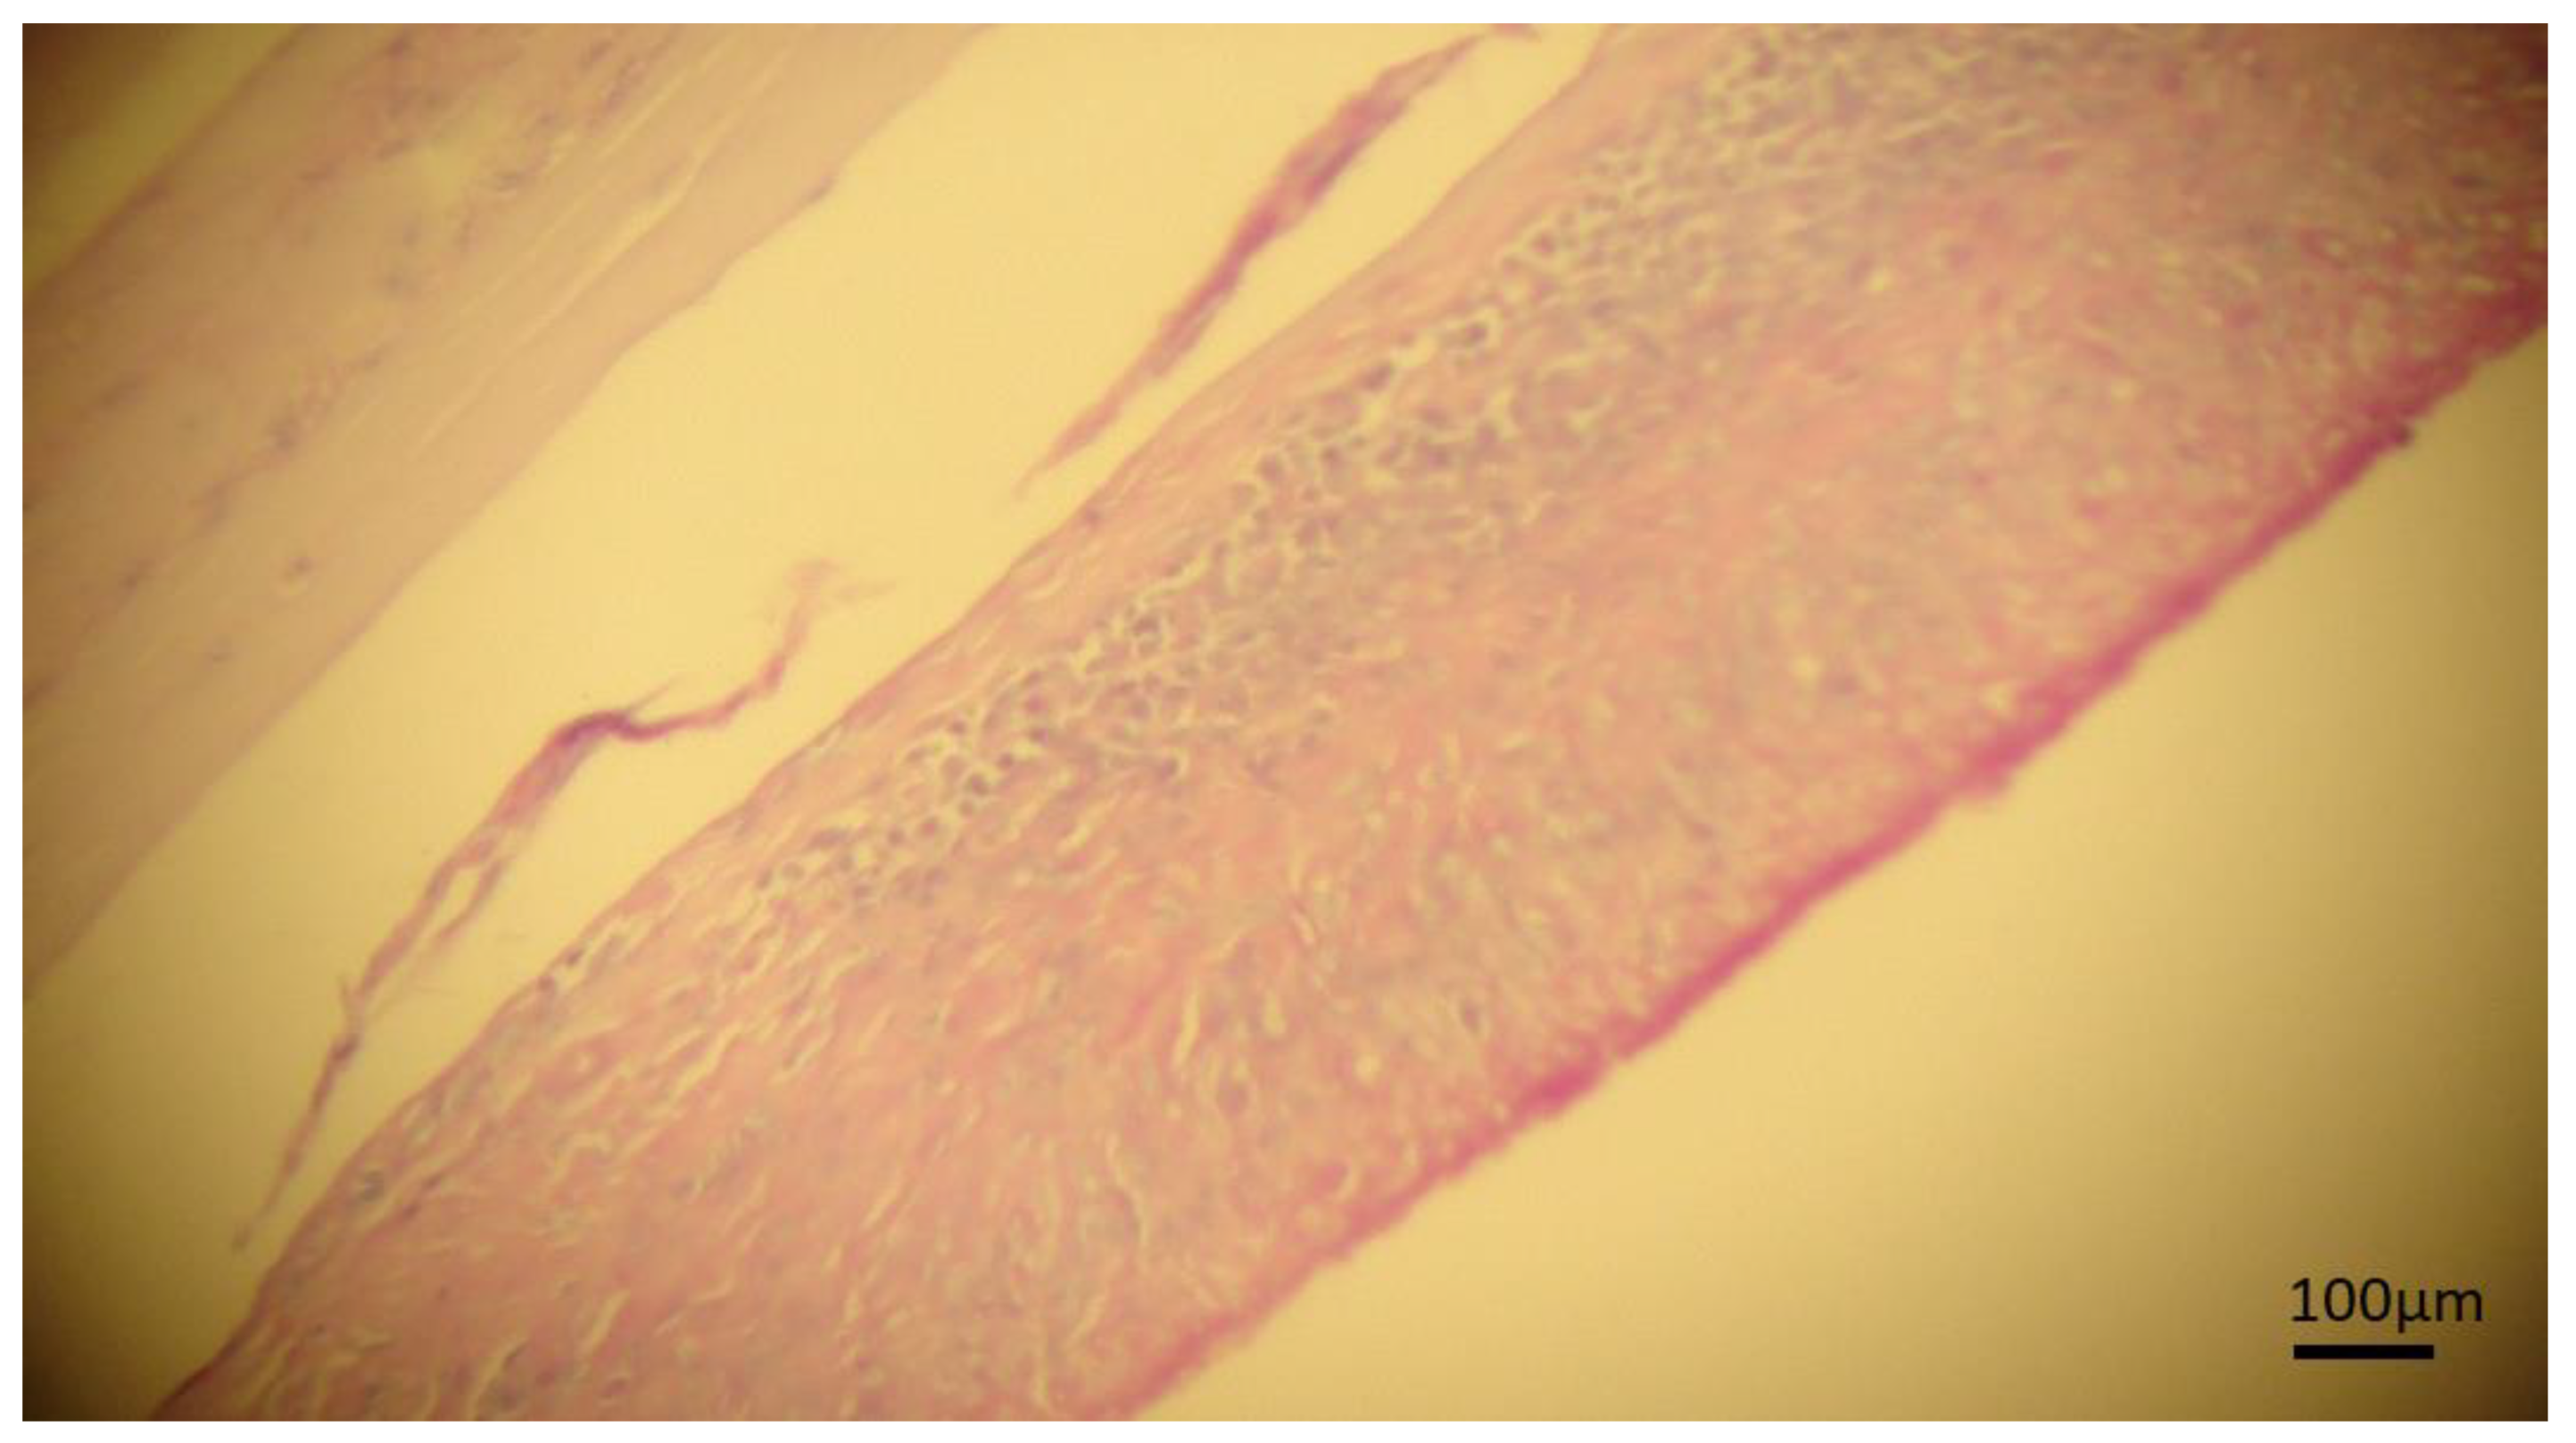

4.3. Histopathological Evaluation

- Costa, R.F.R.; Santos, I.F.; Santana, A.P.; Tortelly, R.; Nascimento, E.R.; Fukuda, R.T.; Carvalho, E.C.Q.; Menezes, R.C. Caracterização das lesões por Cysticercus bovis, na inspeção post mortem de bovinos, pelos exames macroscópico, histopatológico e pela reação em cadeia da polimerase (PCR). Pesq. Vet. Bras. 2012, 32, 477–484. [Google Scholar] [CrossRef]